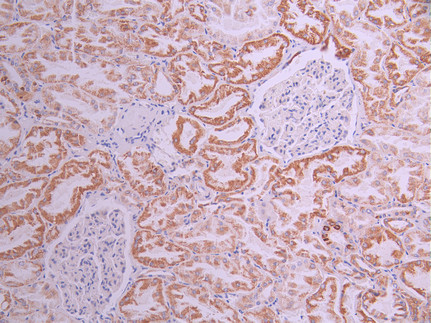

IHC image of CSB-RA961114A0HU diluted at 1:100 and staining in paraffin-embedded human breast cancer performed on a Leica BondTM system. After dewaxing and hydration, antigen retrieval was mediated by high pressure in a citrate buffer (pH 6.0). Section was blocked with 10% normal goat serum 30min at RT. Then primary antibody (1% BSA) was incubated at 4°C overnight. The primary is detected by a Goat anti-rabbit polymer IgG labeled by HRP and visualized using 0.05% DAB.